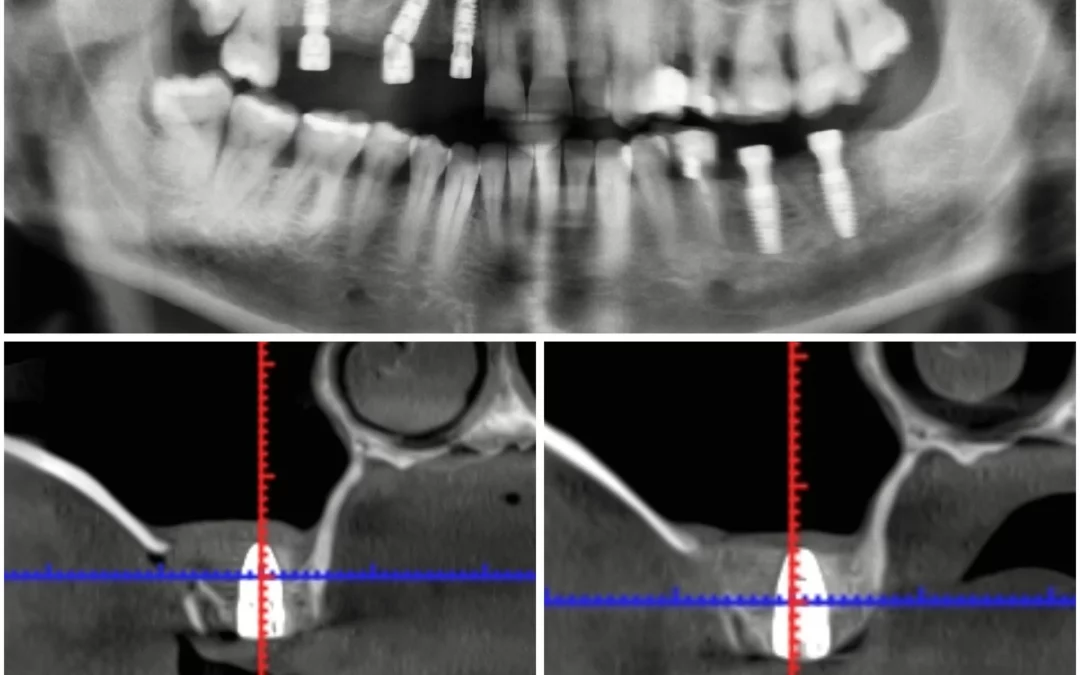

На верхней челюсти установлены три имплантата MIS C1 - Первый имплантат установлен под наклоном в обход гайморовой пазухи (free-hands), использован угловой multi unit. - Второй - в прямой проекции с...